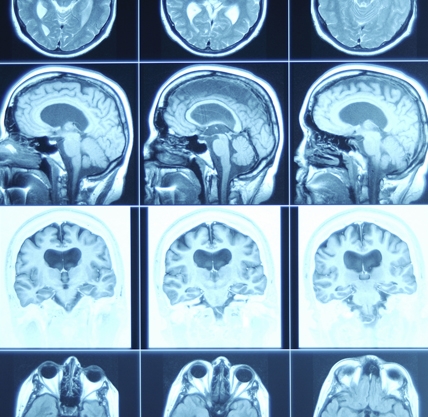

¿Qué es el traumatismo cerebral?

El traumatismo cerebral, también llamado lesión cerebral adquirida o simplemente lesión o trauma cerebral, ocurre cuando un trauma repentino causa daño al cerebro. El daño puede ser focal—limitado a una sola área del cerebro—o involucrar a más de un área del cerebro. El traumatismo cerebral puede resultar de una “lesión cerrada de cabeza” o una “lesión penetrante de la cabeza.” Una lesión cerrada ocurre cuando la cabeza se golpea fuerte y repentinamente contra un objeto pero el objeto no penetra en el cráneo. Una lesión penetrante ocurre cuando un objeto perfora el cráneo y penetra en el tejido cerebral.